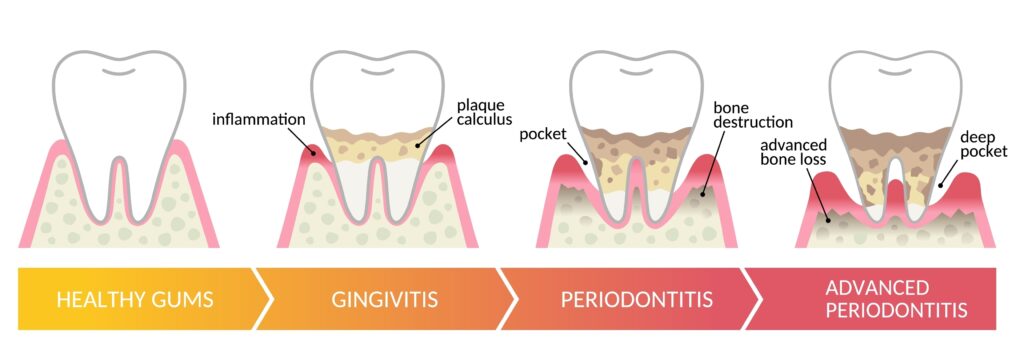

Gum disease, or periodontitis, is an inflammatory condition affecting the tissues around your teeth, primarily caused by plaque buildup. If untreated, it can erode the bone that supports your teeth, leading to tooth loss and further health complications.

Image: stages of gum disease

In some cases of severe periodontitis, the bone in the jaw may have eroded too much to support implants. This makes it crucial to catch and treat periodontitis early to increase the chances of a successful implant treatment.